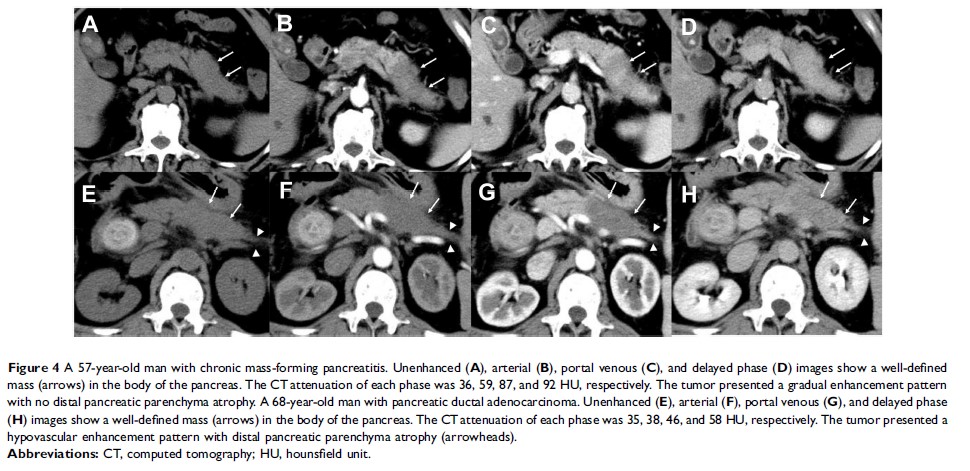

对比增强计算机断层扫描可用于鉴别慢性肿块型胰腺炎与胰腺导管腺癌